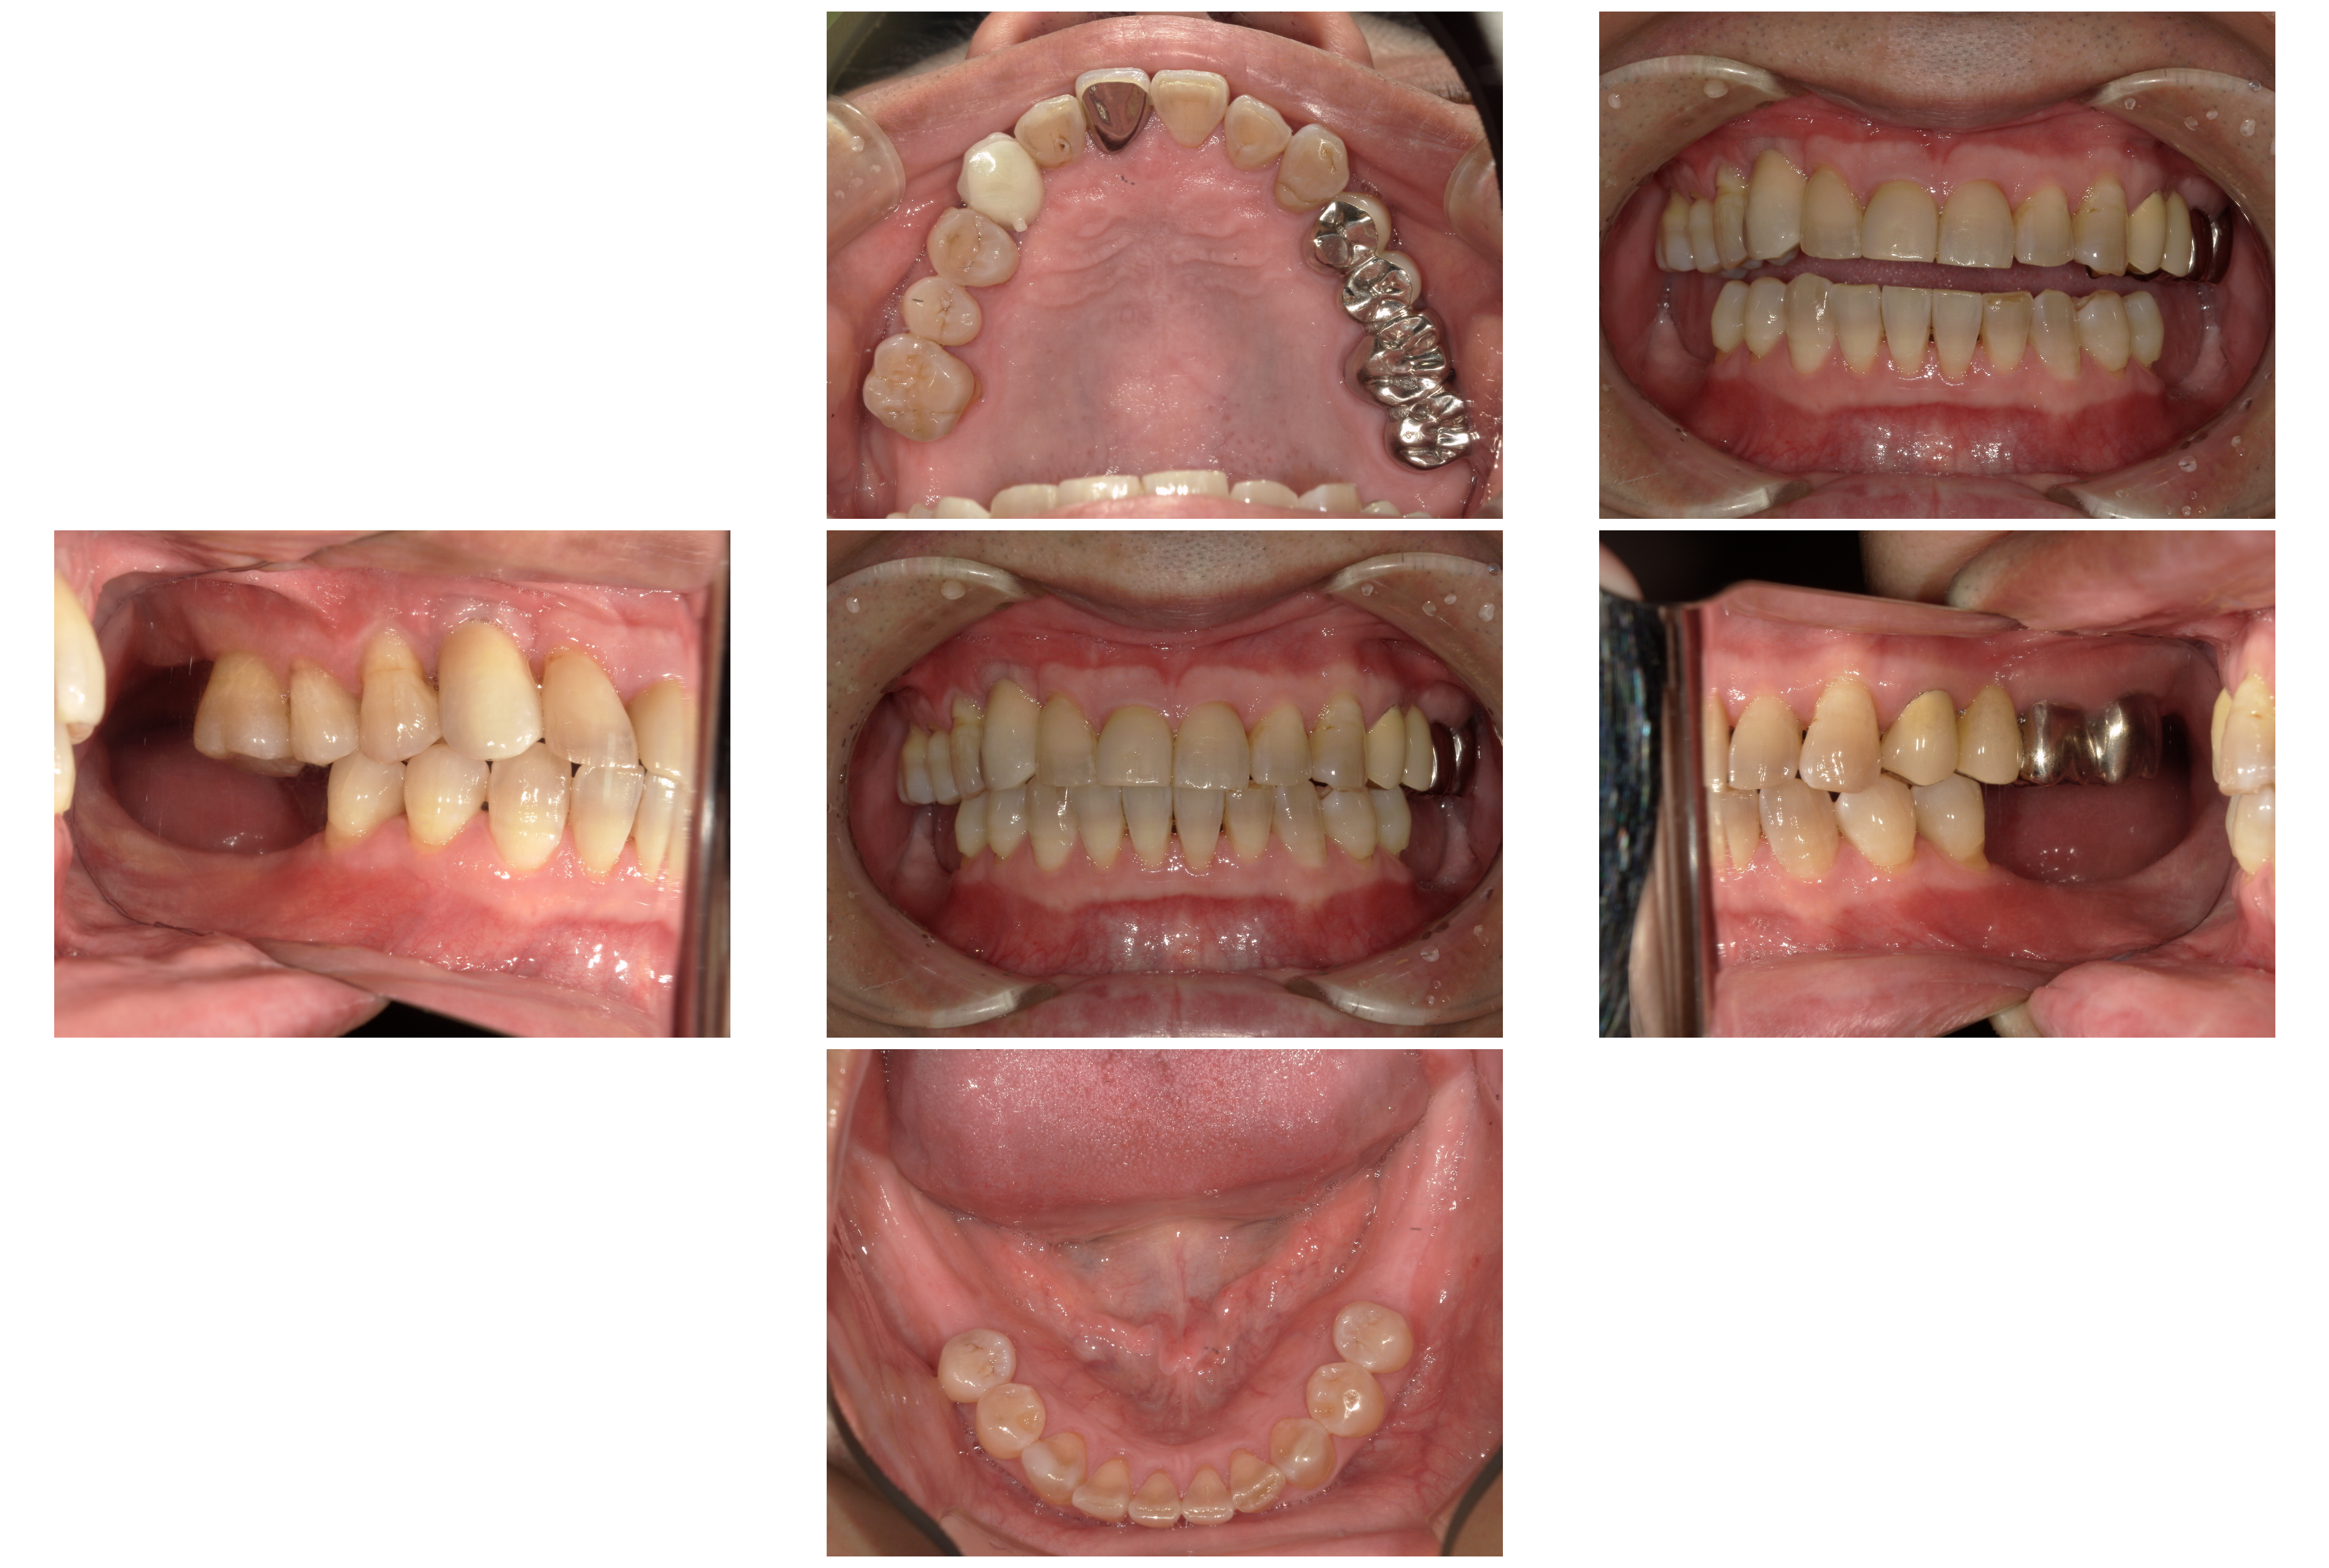

保存が難しい歯をすべて抜歯し、欠損したところは

・右上の前歯をインプラント

・下の両奥歯を義歯

・左上はブリッジ

のコンビネーションで修復しました。

術後

下の奥歯は義歯を使用して頂いています。(写真には写っていません)

治療期間:約2年